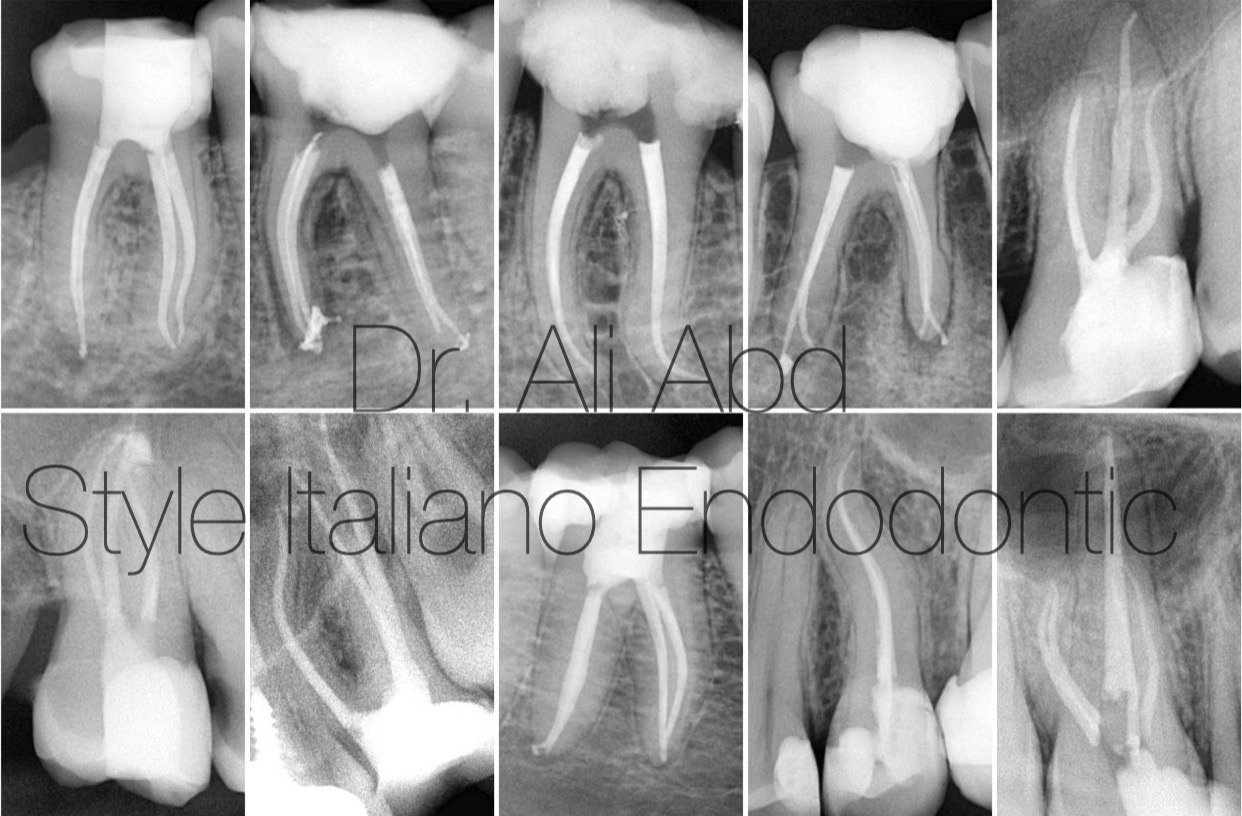

Many cases treated by Manualless shaping technique

Fig. 8